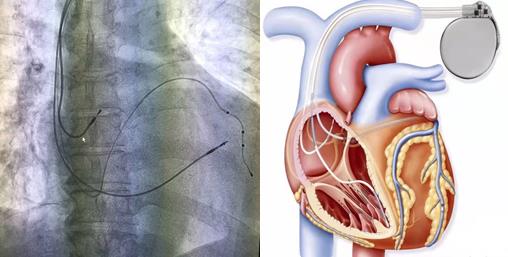

手术过程:手术开始,患者在局部麻醉下,顺利穿刺左侧腋静脉成功后,依次植入右室主动电极、过鞘管送递长鞘、沿长鞘送十极至冠状动脉窦口,推送进冠状窦远端,沿十极电极递送长鞘至冠状窦,取出十极电极,在双导丝支撑下送造影球囊进行造影,选择合适的心左侧静脉后,顺利植入左室电极,再植入右房主动电极,多体位投照各电极位置合适、测试起搏参数均符合要求,遂固定电极后植入起搏器。历经2.5小时, 三腔起搏器植入术顺利完成,患者各项参数检测均正常。

目前常用的“单(双)腔心脏起搏器”均只能治疗心动过缓,但三腔起搏器可实现心脏再同步化治疗(CRT)目的,不但具有治疗心动过缓的功能,还能解决由于患者左右心室收缩不同步而导致的心衰症状。它是在传统的双腔起搏(右心房,右心室起博)的基础上增加了左心室起搏,左室起搏电极经右房的冠状静脉窦开口,进入冠状静脉左室后侧壁支起搏左室,通过多部位起搏恢复左右心室同步收缩,增加左心室充盈时间,减少室间隔矛盾运动,减少二尖瓣返流,从而改善患者的心脏功能,甚至可以让扩大的心脏回缩,提高运动耐量以及生活质量。